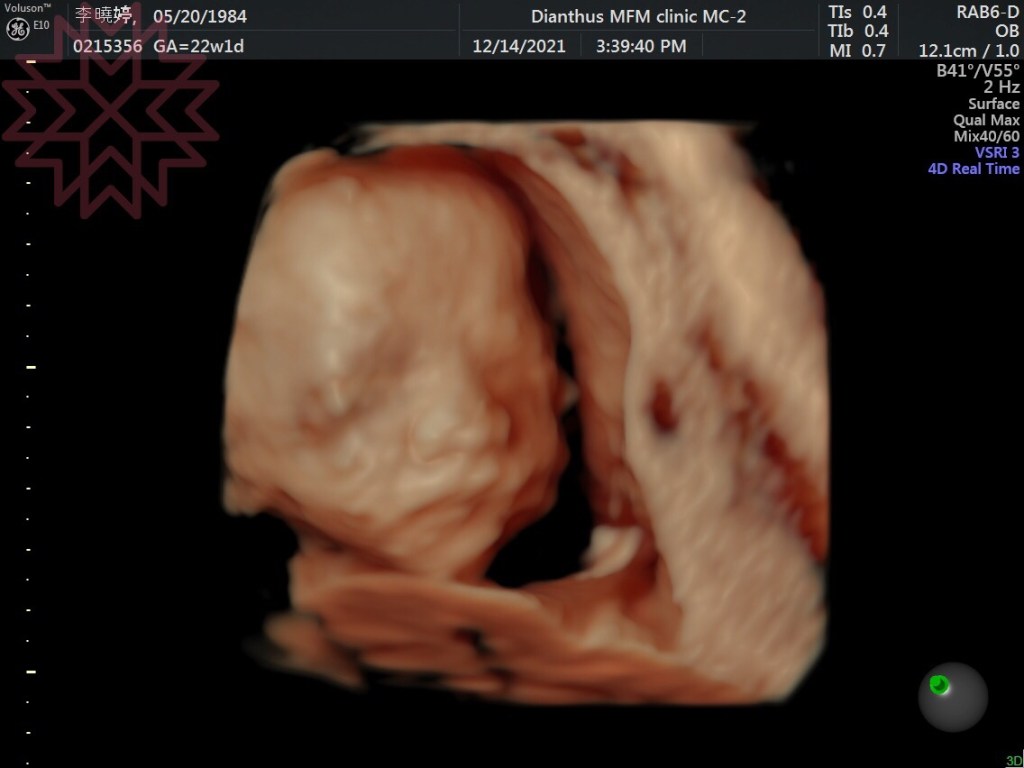

白雲20週,6個月了,剛做完【非侵入性胎兒梁色體檢測】(NIPT)目前為止都是非常健康。接下來過幾週,就是高層次超音波、妊娠糖尿檢查,還有定期量血壓,以及每次的產檢是否都能過關!白雲阿,爸爸媽媽都很愛你喔,期待你平安健康的到來,藍天會是一個很棒的哥哥,負責任、有同理心、有自信的手足!白雲會是一個真誠、尊重、內心強大的男人,2個會相親相愛! !

照太久(雖然才1小時)白雲直接轉身不給照(藍天是苦瓜臉)

爸爸說,白雲看起來比藍天還要胖一點